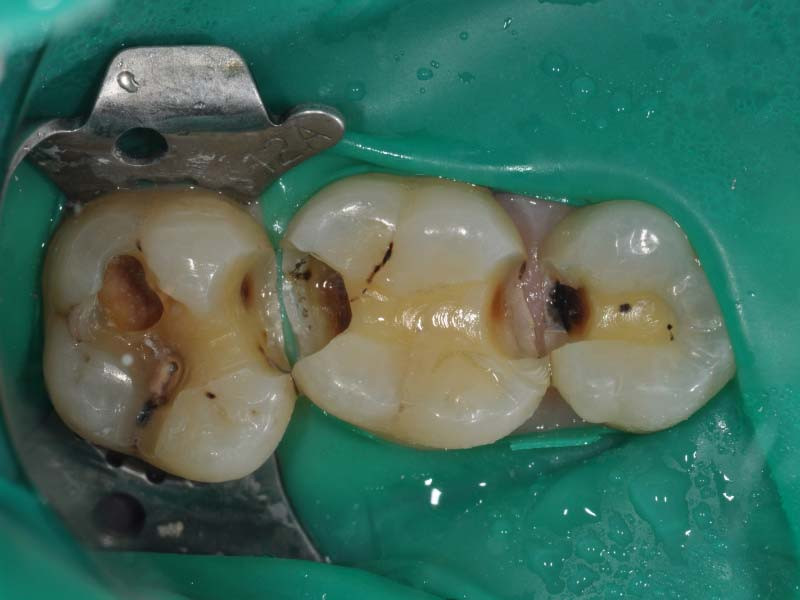

Before

牙齒蛀牙範圍大且深